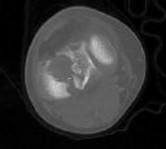

**CLINICAL SITUATION**

Figures 1 and 2 are the radiographs of a 35-year-old man who is brought into the emergency department after a motor vehicle collision. He is complaining of isolated knee pain. Examination reveals swelling, blood filled blisters, popliteal ecchymosis, joint line pain, and limited knee joint motion. His pulses and sensation are normal.

Figures 3 through 8 are the axial and sagittal CT scan sections of the injury. Intra-operative patient positioning for definitive fixation should be

Figures 1 through 3 are the radiographs of a 25-year-old man who is brought to the emergency department after a motorcycle collision. He is complaining of isolated knee pain. Examination reveals swelling, popliteal ecchymosis, joint line pain, and limited knee joint motion. His pulses and sensation are normal.

Figures 4 through 8 are the axial and coronal CT scan sections of the injury. Intra-operative patient positioning for definitive fixation should be